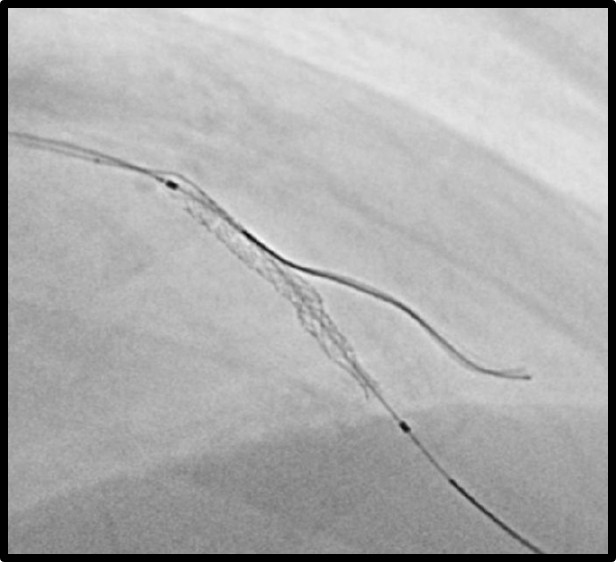

A 6 Fr guiding catheter was engaged in the left coronary ostium, and a 0.014-inch guidewire was advanced into the distal LAD. The first diagonal branch (D1) was protected by the jailed balloon technique, and direct stenting was performed. A drug-eluting stent was positioned at the target lesion; however, during balloon inflation, a pinhole rupture occurred in the stent-mounted balloon, resulting in incomplete expansion limited to the proximal segment.

After the rupture, we replaced the inflator with one filled with undiluted contrast medium to improve pressure transmission. The balloon was then inflated at high pressure, which partially expanded the stent. Subsequently, we used a semi-compliant balloon for post-dilatation, achieving complete stent expansion without angiographic complications. Final angiography confirmed optimal stent deployment and TIMI 3 flow. The patient remained hemodynamically stable throughout the procedure and experienced no post-procedural complications.